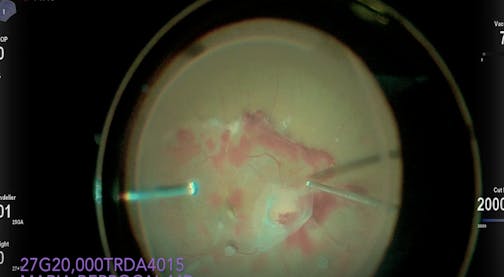

Dr. Berrocal 27G HyperVit TRD VH w/ DATAFUSION

Maria Berrocal, MD